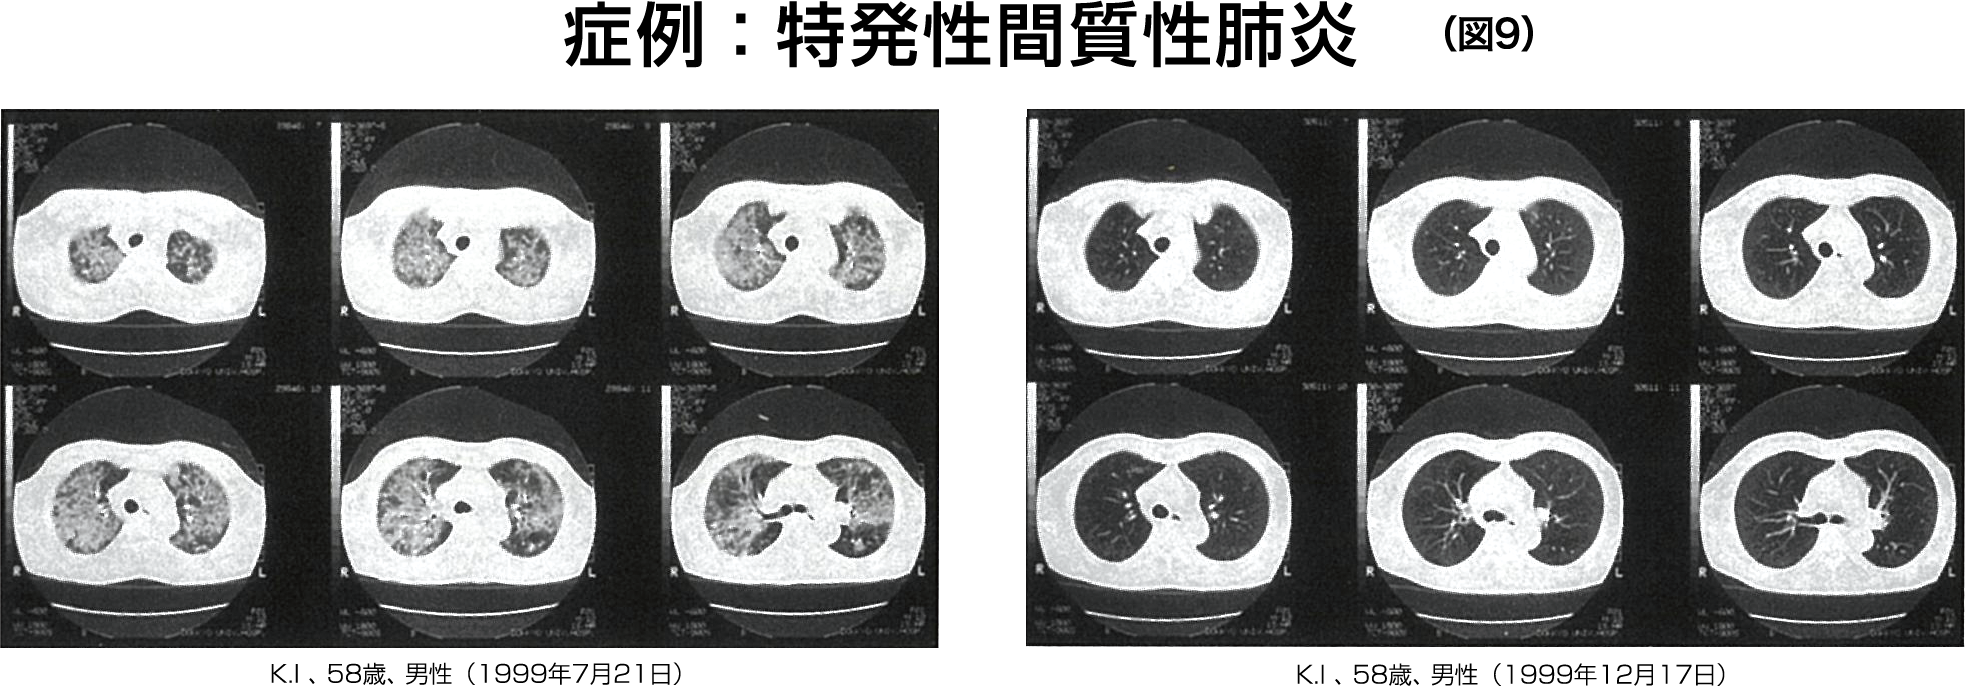

約1カ月後の同年12月17日の胸部CT所見では、明らかな改善所見を示した。 約5カ月後には自覚症状もほぼ消失した。

胸部CT所見(図9):図9上段は急性増悪時のCT所見では、全肺野にスリガラス陰影が認められる。 その後、ステロイドパルス療法により軽快したが、労作時の息切れと咳が改善しないため、ノブドウ抽出液製剤の投与を開始したところ、約1カ月後の1999年12月17日の胸部CT所見を図9下段に示す。

図9上段に認められていたスリガラス陰影はほぼ消失し、明らかな改善所見を示した。 本症例で、筆者らがはじめて間質性肺炎患者にノブドウ抽出液を投与し効果を評価した。 その結果、間質性肺炎の急性増悪を乗り切った後の慢性病変に対し、有効性を示唆する結果が得られた。 今後、症例数を増やして検討することが重要であると思われる。

ノブドウ抽出液製剤投与前後の胸部CT所見

上 段:急性増悪時(1999年7月21日)

下 段:ステロイドパルス投与後のノブドウ抽出液製剤投与1カ月後(1999年12月17日)

急性期には全肺野にすりガラス陰影を認め、その後のノブドウ抽出液製剤投与後にはすりガラス陰影は消失している